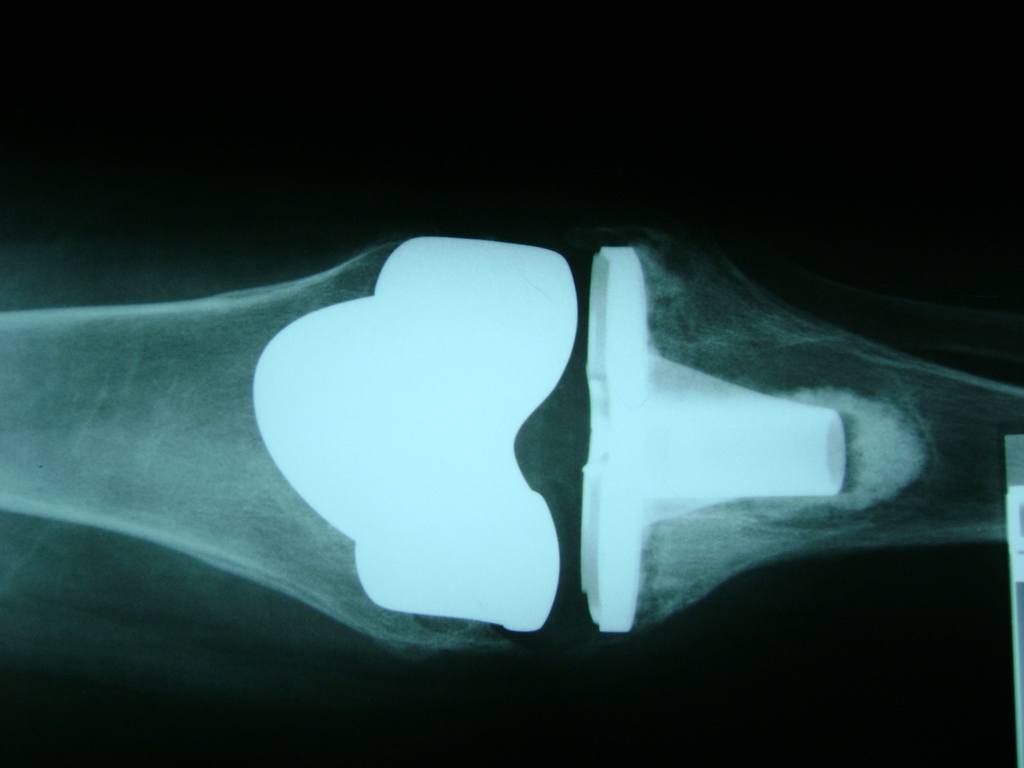

Cirugías de Calcaneo - Rodilla

La artroscopia de rodilla es un cirugía en el cual la estructura interna de la articulación es examinada ya sea para realizar un diagnostico o para realizar un tratamiento, este procedimiento se realiza utilizando un instrumento parecido a un pequeño tubo llamado artroscopio.